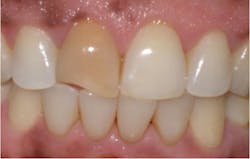

The second most common stain is brown stain.1 Clinically, it may range in appearance from light to dark brown or black and may appear leathery. Brown stain is distributed primarily on the cervical third of lingual tooth surfaces but may extend to the middle third. The deposits increase with poor oral self-care or neglect. Brown stain is primarily caused by smoking or chewing tobacco, hookah, and marijuana use1-4 (figure 2). Other brown stains are caused by stannous fluoride, foodstuffs (coffee, tea, soy sauce), betel nut chewing, swimmer’s stain (from frequent exposure to chlorinated or brominated pool water), and antiplaque agents (chlorhexidine gluconate mouth rinse) (figure 3).1,3,4 The best way to prevent brown stain is to reduce or eliminate the cause of the stain. It can also be reduced by improved oral self-care. Removal is accomplished with powered and manual instrumentation as well as polishing.